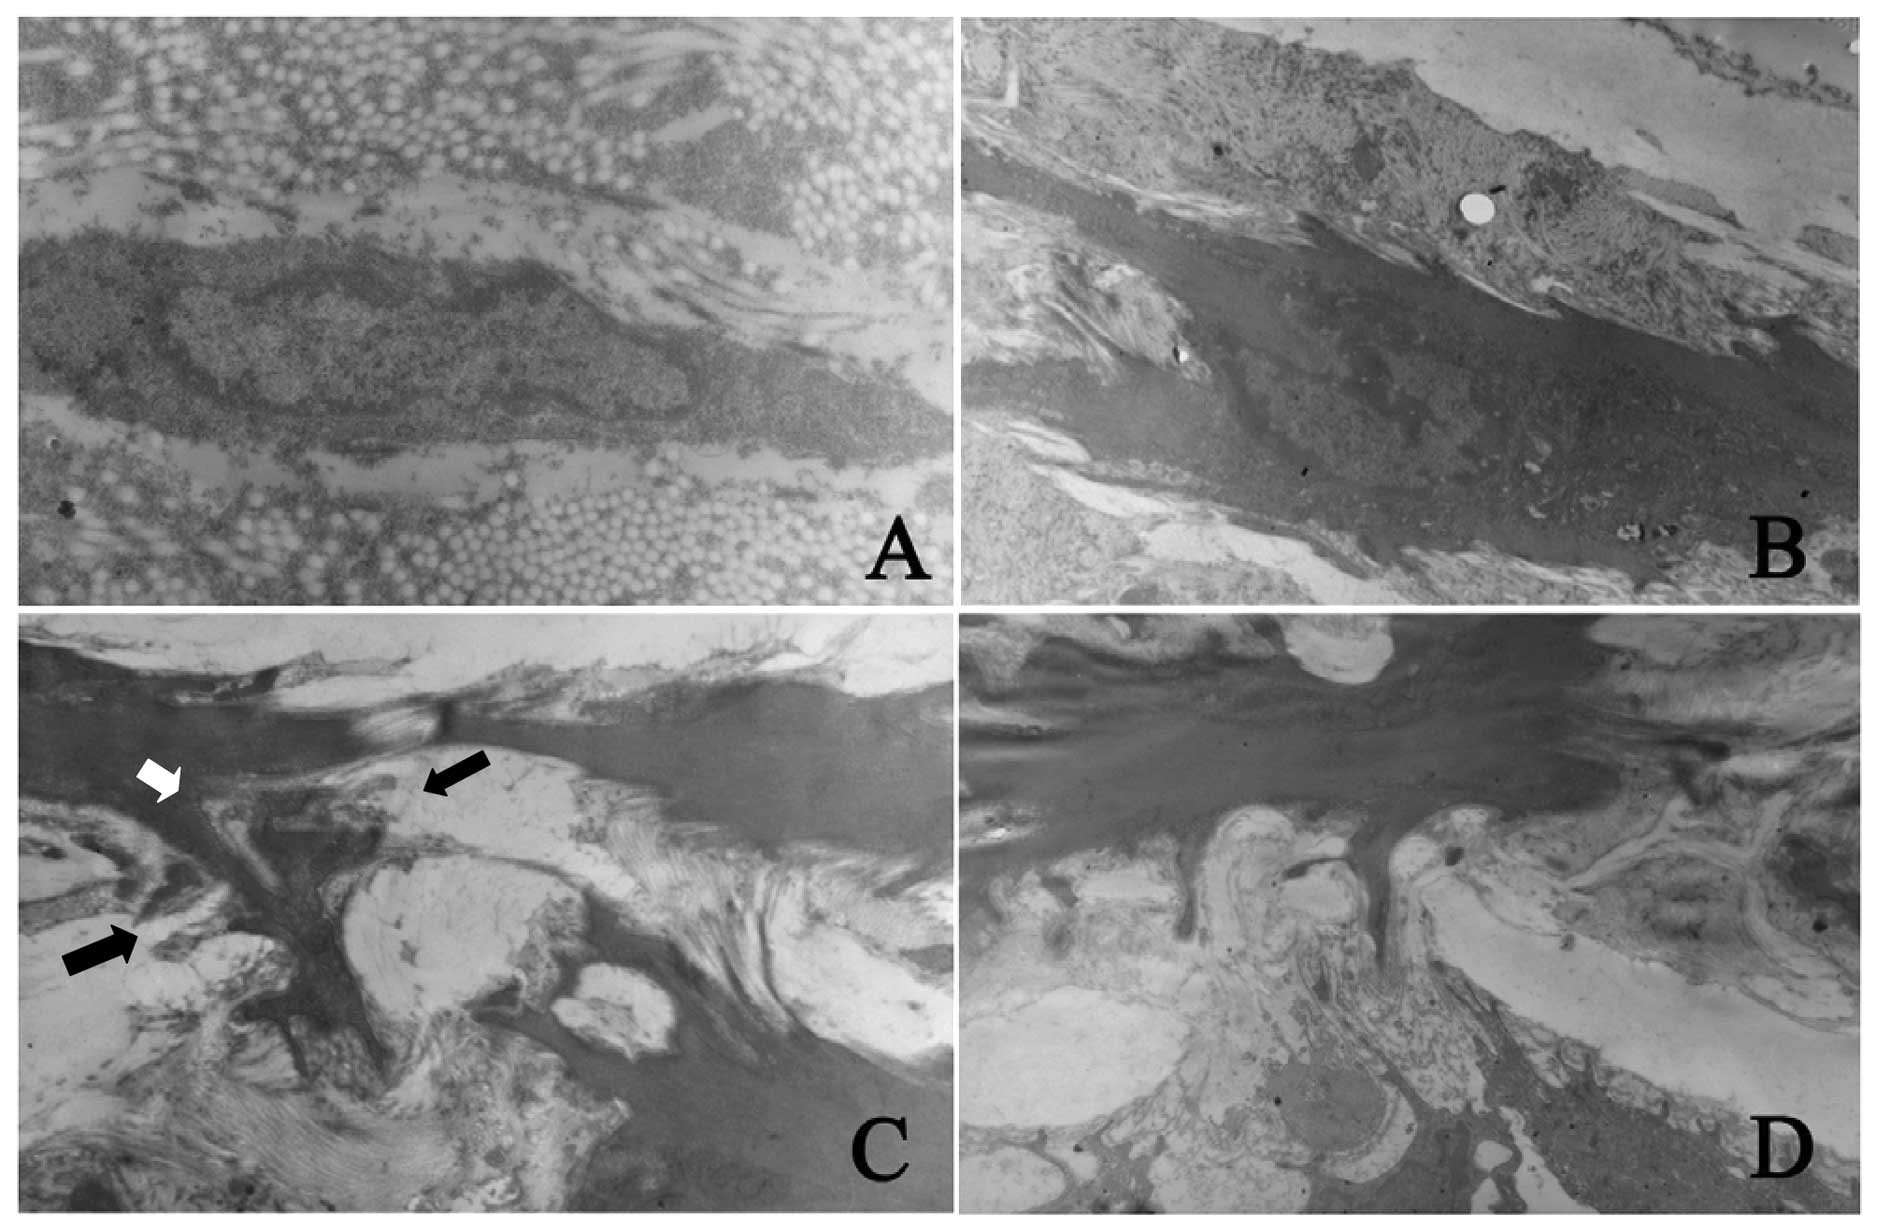

Three days after PTA, the fibroblasts in the adventitia exhibited a mature phenotype in the control group. The cells and nuclei were long-spindle-shaped and the cells had less pseudopod-like processes and less cytoplasm. After arterial injury, the spindle-shaped fibroblasts were found in the adventitia and the collagen and pseudopod-like processes increased. Seven days after PTA, cells with different shapes and sizes were found and the nuclei were irregular and spindle-like. These cells were noted to be myofibroblasts. These cells had processes with varied sizes and the number of processes increased and formed lamellipodia stretching to the external elastic lamina and crossing the fenestra of the external elastic lamina. These cells had a tendency to migrate from the adventitia into the media. Fourteen days after PTA, the intima was markedly thickened and spindle-like and oval myofibroblasts were noted. The longitudinal axis of cell growth was vertical to the internal elastic lamina. Changes in the ultrastructures of the myofibroblasts were similar to those 7 days after PTA, but the distribution of intrinsic structures in the artery was different. At 14 days after PTA, the number of cells in the media and intima increased and the fenestra of internal elastic lamina enlarged. In the intima, myofibroblasts formed several processes and the lamellipodia stretched to and crossed the external elastic lamina. These cells had a tendency to migrate into the intima (Fig. 3). Twenty-eight days after PTA, the myofibroblasts in the different vascular layers transformed reversely into fibroblasts which were characterized by small nuclei, less nucleoplasm, small but obvious nucleoli and less cytoplasm. In addition, the number of pinocytotic vesicles was reduced and the lamellipodia almost disappeared in these cells.

Figure 3.

Detection of morphological changes and migration of fibroblasts after PTA by scanning electron microscopy. (A) The adventitial fibroblasts in normal blood vessels had a contractile quiescent phenotype. These cells had long-spindle nuclei but had less pseudopod-like processes (magnification, x15,000); (B) 7 days after PTA, the myofibroblasts in adventitia found processes with different sizes and the processes increased (magnification, x7,000); (C) 7 days after PTA, the myofibroblasts in adventitia formed a lot of processes and the lamellipodia (white arrow) crossed the fenestra of external elastic lamina (black arrow). Cells had a trend to migrate from adventitia into media (magnification, x10,000); (D) 14 days after PTA, the fenestra of internal elastic lamina enlarged and the myofibroblasts in the media formed several processes. The lamellipodia crossed the fenestra of internal elastic lamina (as in C). Cells had a trend to migrate from media into intima (magnification, x10,000).

The migration of proliferating adventitial cells into the intima following arterial injury is still controversial (18–23). Our findings suggest that proliferating adventitial cells migrate into the intima and are the main source of newly generated intima. At 3 days after PTA, the proliferating cells were mainly found in the adventitia. Seven days after PTA, the number of proliferating cells in the adventitia reached a maximal level and these cells were mainly found around the external elastic lamina and the proliferating cells in the media began to increase. At 14 days after PTA, the proliferating cells in the adventitia reduced but those in the media and intima were markedly increased. The number of BrDU-positive cells in both the intima and media reached a peak at this time point and the thickness of the intima was maximized. At 28 days after PTA, the BrDU-positive cells in the adventitia, media and the newly generated intima were significantly reduced and the proliferating cells were almost absent in the adventitia and media. Analysis of the BrDU-positive cells in the different vascular layers showed that the number of BrDU-positive cells increased sequentially and alternatively: the increase in BrDU-positive cells in the media and newly generated intima occurred when the proliferating cells in the adventitia began to decrease. This may be explained by the fact that the myofibroblasts in the vascular adventitia migrated into the media and intima. These findings are consistent with those in a study by Scott et al. Smearing CCAs with BrDU solution can directly and effectively label myofibroblasts. Of note, in the present study, smearing CCAs with BrDU immediately after PTA only labeled the adventitial cells and labeling was not performed later. Thus, we must address the question of the origin of the the BrDU-positive cells in the newly generated intima 7–14 days after PTA. We speculate that the BrDU cells in the vascular adventitia proliferated and migrated from the adventitia into the intima, which is also supported by other studies (24). In addition, as noted at high magnification under a light microscope, a large amount of BrDU-positive cells in the newly generated intima with thickening were short-spindle-like and had full cytoplasm. These morphological features significantly resembled those of long-spindle-like VSMCs in the media, and suggest that these cells are similar to myofibroblasts in the vascular adventitia. Results in other studies also support our findings; following VSMC activation under in vitro control, stimulation of the vascular adventitia could induce the migration of characteristic fibroblasts in the adventitia (25). Following transfection with a retrovirus carrying the β-galactosidase LacZ gene, primary fibroblasts in the adventitia were inoculated into the adventitia of rat CCAs to induce LacZ expression. In situ hybridization was employed to monitor the myofibroblasts. Results showed LacZ expression in the injured intima. In newly generated intima, the morphology of LacZ-positive fibroblasts was similar to adventitial cells indirectly labeled with BrDU. These findings indicate that the newly generated intima had cells derived from the adventitia (26,27). In addition, we also observed findings similar to those in the study of Scott et al (4). The nuclei of BrDU-positive cells in adventitia, media and intima became light from 3 to 28 days after PTA. This implies that, from 3 days after PTA, the BrDU-labeled myofibroblasts in the adventitia migrated into the newly generated intima in which they underwent division, replication and proliferation. Thus, these cells lose BrDU-labeled DNA. These findings suggest that proliferating adventitial cells migrate from the adventia and cross the external elastic lamina and become the main cells in the newly generated intima. Additionally, electron microscopy showed, 7 days after PTA, that the myofibroblasts in the adventitia formed lamellipodia which stretched to the external elastic lamina and crossed the fenestra of the external elastic lamina. These cells had a tendency to migrate into the media. At 14 days after PTA, the fenestra of the internal elastic lamina in the media enlarged. The myofibroblasts formed lamellipodia with several processes which stretched to the internal elastic lamina and crossed the fenestra of the internal elastic lamina. These cells had a tendency to migrate into the intima.